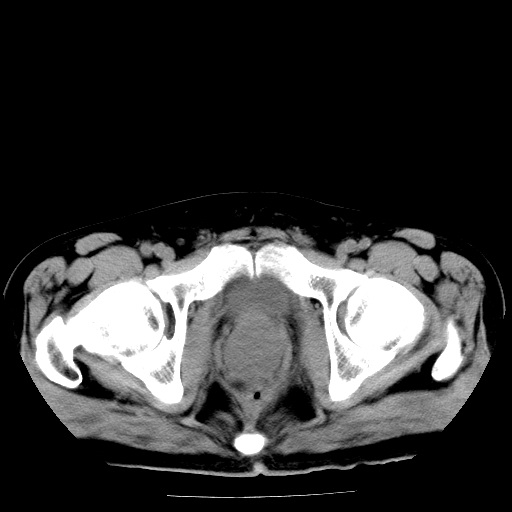

男,66岁,直肠癌术后一个月,化疗前ct检查。

前列腺大,直肠壁厚,造瘘术后

直肠癌造瘘术后改变,周围淋巴结转移

前列腺肥大

直肠癌造瘘术后改变,盆腔多发淋巴结转移

直肠癌造瘘术后改变,直肠周围软组织增厚,盆腔多发淋巴结转移。前列腺肥大。

结肠造瘘术后。

直肠癌周围浸润。

前列腺肥大。